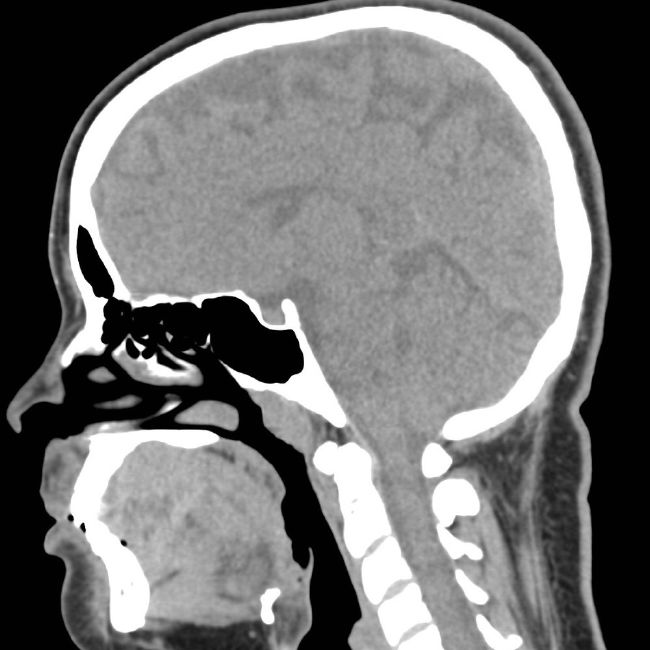

Заболевания, травмы структур мозга являются одной из наиболее серьезных патологий организма. Среди сосудистых нарушений лидирующие позиции занимает инсульт, пороки мозговых сосудов. Компьютерная томография обладает значительными ресурсами для быстрого выявления нарушений, сбора важных диагностических данных за минимальный период, что особо ценно при экстренных состояниях.

Современные медицинские центры, владеющие высокотехнологичным оборудованием, позволяют провести мониторинг состояния структур головного мозга, костей черепа, кожи и подкожной клетчатки, вовремя обнаружить новообразования. Важно, чтобы специалист, курирующий процедуру, обладал достаточной квалификацией, опытом, знаниями не только для корректного обследования, но и для расшифровки результатов.

Работа компьютерного томографа базируется на просвечивании тонким рентгеновским лучом нужной области тела. Коэффициенты поглощения трансформируются компьютером в картинку на мониторе, что позволяет провести визуальный, количественный анализ. Основной задачей исследования является определение патологических изменений в тканях, их точная локализация, количество, форма, размеры, интенсивности тени, четкости контуров.

Желание понять строение, функции головного мозга существовало еще с древних времен. В XX веке с внедрением в медицинскую практику метода компьютерной томографии произошел настоящий прорыв. Технология позволяет точно оценить состояние, определить патологические очаги многих структур головы:

• мозга;

• черепа;

• кожи и подкожной клетчатки;

• челюстной системы;

• зубов;

• глазниц;

• носа, придаточных пазух.

Метод очень информативен при обнаружении новообразований, развитии воспалительных мозговых процессов, для мониторинга последствий травм. Он лучше, чем МРТ, подходит для анализа ЛОР-органов, получения диагностических данных при головных болях после травматизации, подозрении на онкологию. Метод не имеет абсолютных противопоказаний, но в ряде случаев необходимо соотнести пользу полученных данных и потенциальный вред, целесообразность применения (при беременности, лактации, некоторых хронических заболеваний, аллергии, индивидуальной непереносимости контрастного вещества.